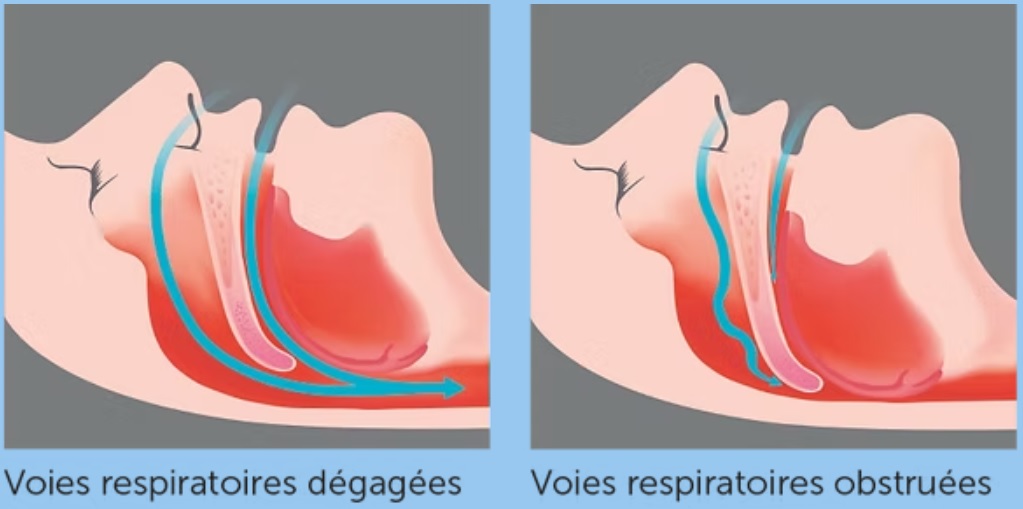

Le Syndrome d’Apnée Obstructive du Sommeil (SAOS) se caractérise par des pauses respiratoires dues à une obstruction des voies aériennes. Serenight© aide à maintenir ces voies ouvertes pour améliorer la respiration et le sommeil.

Serenight© a mis au point une thérapie efficace grâce à son système exclusif d’orthèses mandibulaires. Une alternative de choix après refus ou intolérance au traitement par pression d’air positive (CPAP). Pendant le sommeil, Serenight© empêche l’affaissement et le recul de la mâchoire inférieure. Il permet de maintenir ouvertes les voies respiratoires avec un maximum de confort et de sécurité.

Pendant le sommeil, Serenight© empêche l’affaissement et le recul de la mâchoire inférieure. Il permet de maintenir ouvertes les voies respiratoires avec un maximum de confort et de sécurité.

- Il éloigne mécaniquement la langue des voies respiratoires.

- Il améliore le flux et le volume d’air inspiré.

- Il rend la respiration libre d’apnée et de ronflement.

L’OAM avance légèrement la mâchoire inférieure pour libérer les voies respiratoires et prévenir leur obstruction pendant le sommeil. Ce mécanisme réduit les ronflements et prévient les apnées du sommeil, en améliorant l’apport en oxygène et la qualité globale du sommeil. Confortable et fabriquée sur mesure, elle est une solution efficace pour les personnes souffrant de ronflements chroniques ou de syndrome d’apnées obstructives léger à modéré.